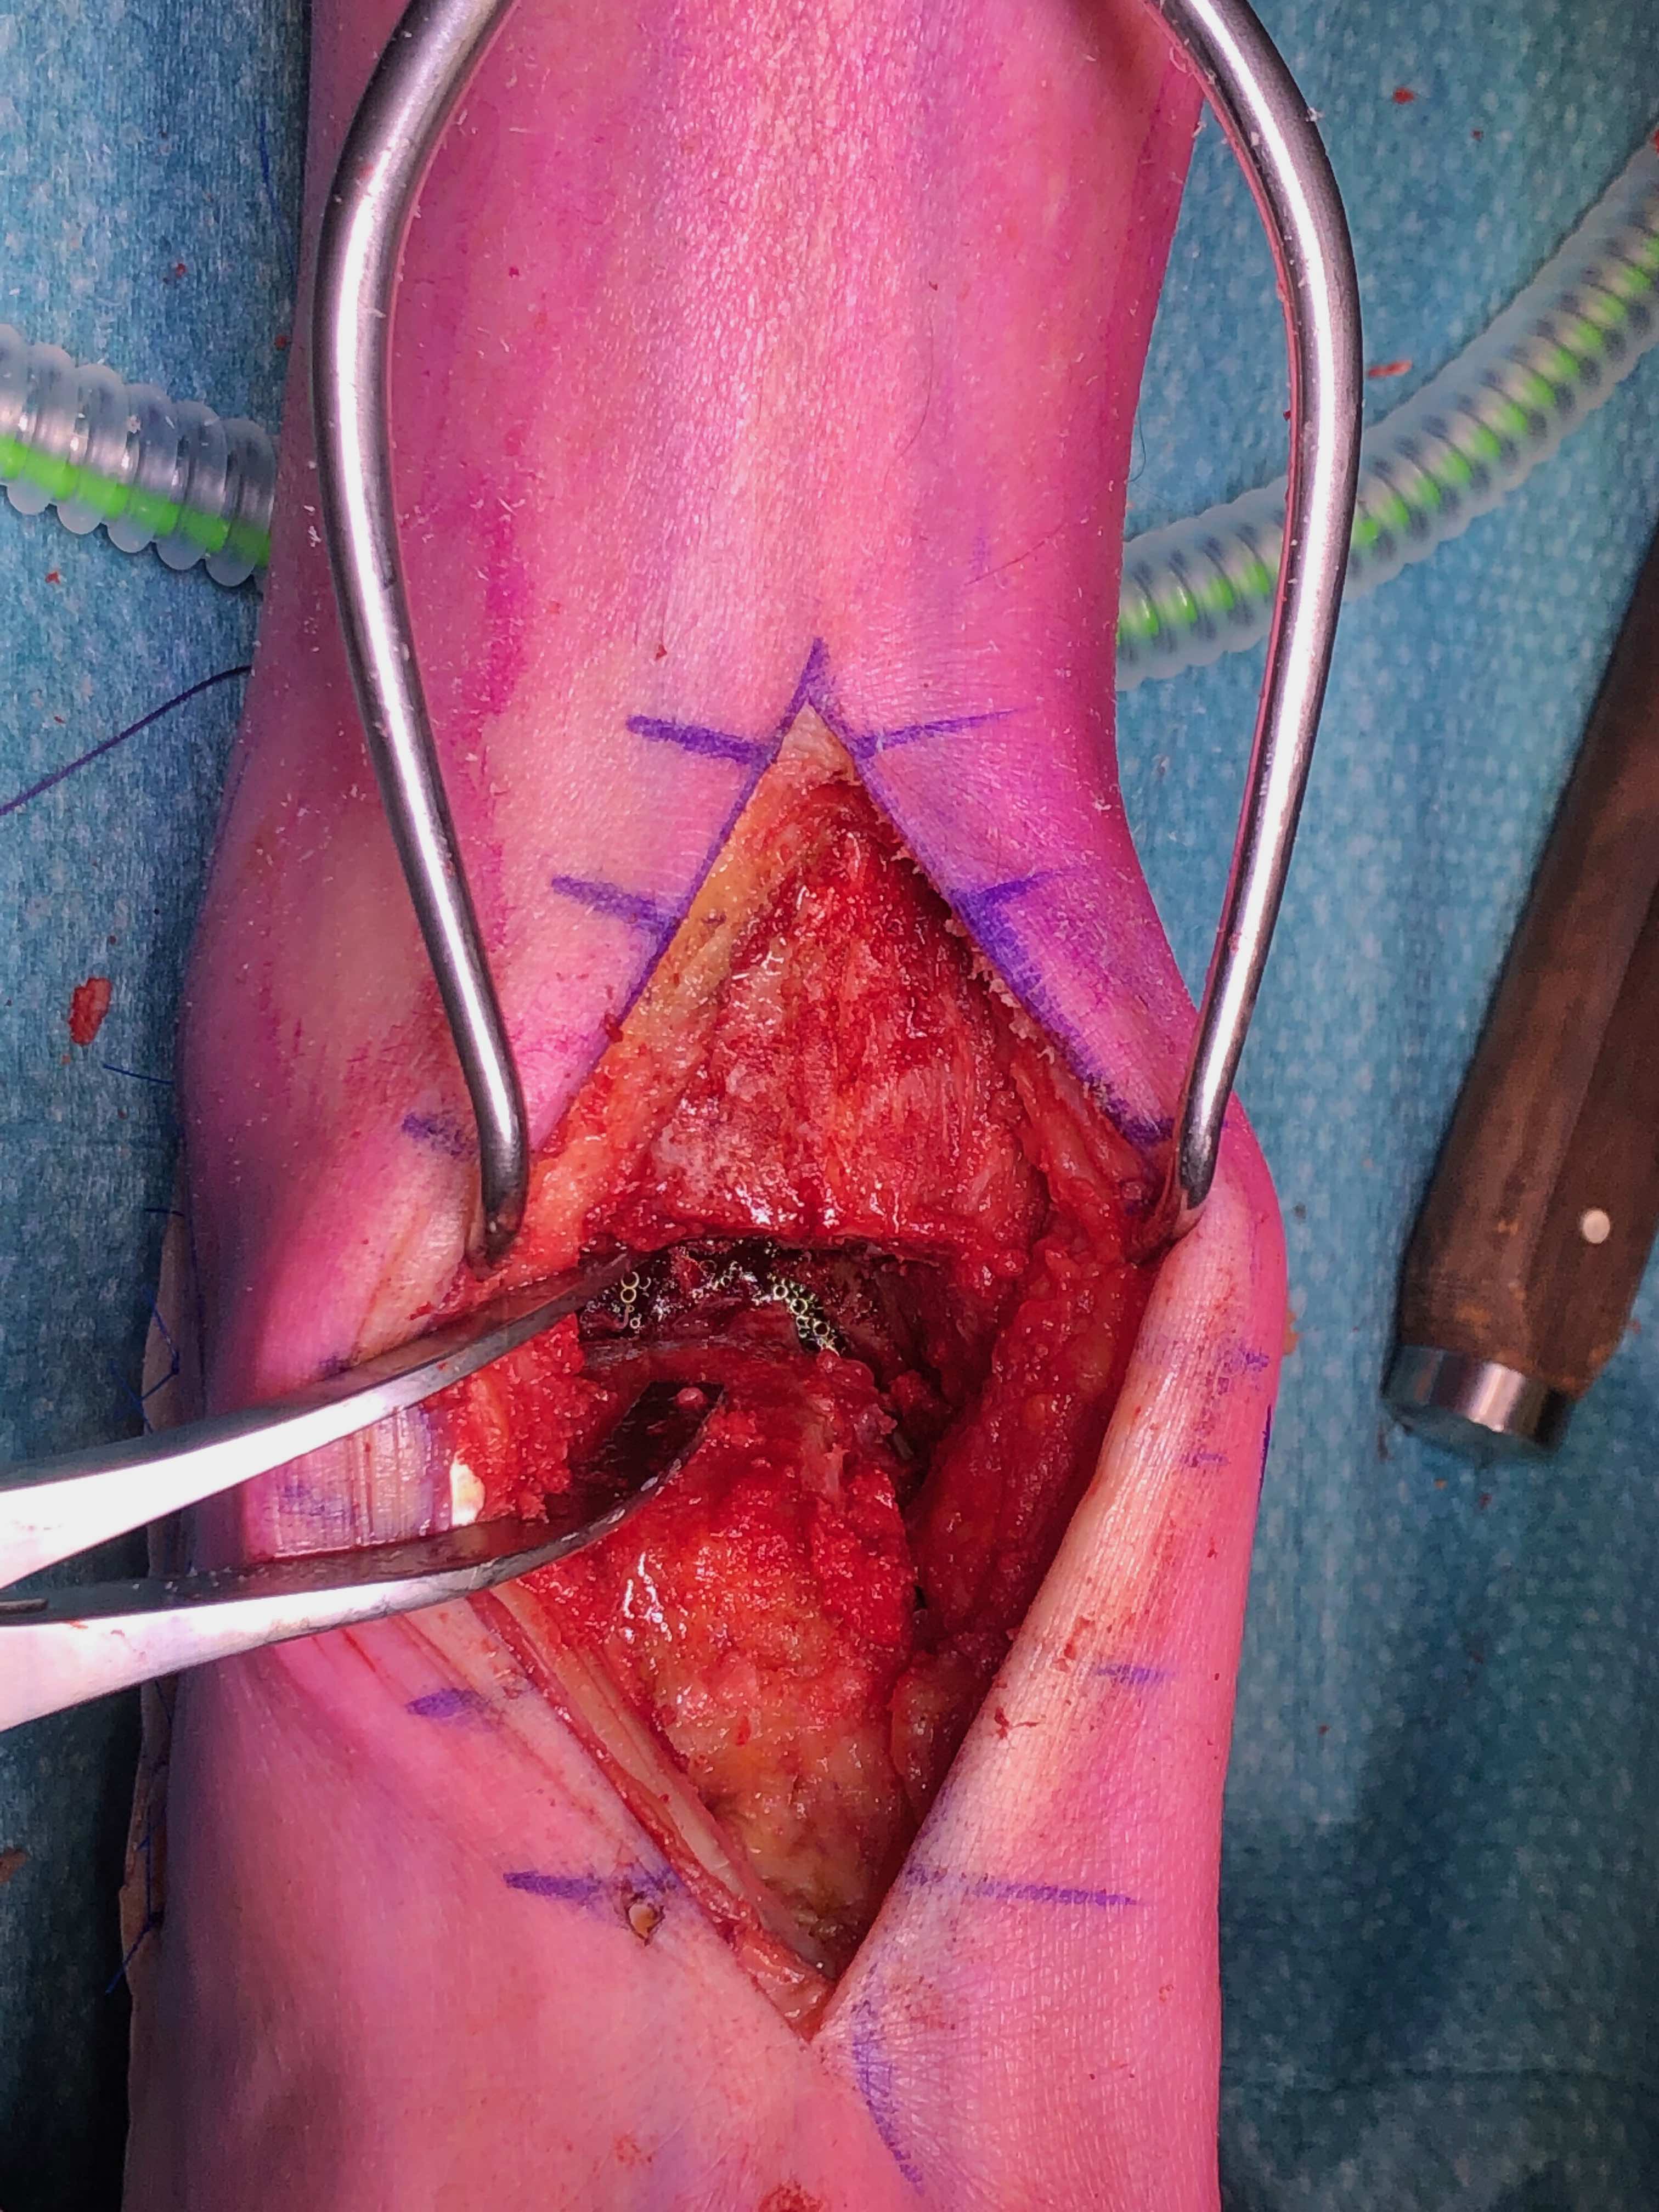

Transfibular

Technique

Incision over distal fibula, curved forward over subtalar joint

- subperiosteally expose distal fibula

- protect peroneal tendons posteriorly

- oblique osteotomy 6 cm above joint

- can externally rotate fibula +/- remove medial half +/- resect distal fibula

- insert lamina spreader / distractor into joint

- use oscillating saw / burr to prepare joint surfaces

- protect medial malleolus

+/- Anteromedial incision to prepare medial gutter

- medial to tibialis anterior, protect saphenous nerve and vein

- protect deltoid ligament (provides blood supply to talus)

Fixation

- position foot, check with image intensifier

- +/- bone graft

- two cannulated screws from medial tibia to talus dome / neck

- +/- screw medial malleolus to talus

- +/- screw fixation fibular / onlay graft